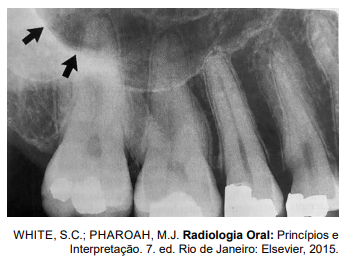

Analise a imagem radiográfica a seguir.

As estruturas anatômicas apontada pelas setas pretas correspondem ao

As estruturas anatômicas apontadas pelas setas pretas correspondem aos